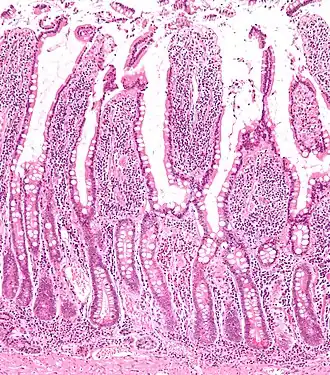

![]() Микропрепарат стенки тонкой кишки | |

Стенка тонкой кишки образована слизистой оболочкой, подслизистой основой, мышечной и серозной оболочками.

Слизистая оболочка тонкой кишки характеризуется характерным рельефом, образуемым наличием целого ряда анатомических образований: циркулярных складок, ворсинок и кишечных желез или крипт. Благодаря этим структурам увеличивается общая, в том числе и всасывающая поверхность, что способствует выполнению основных биологических функций тонким отделом кишечника[4]:

- циркулярные складки (лат. plicae circulares) сформированы слизистой оболочкой и подслизистой основой тонкой кишки;

- кишечные ворсинки (лат. villi intestinales) образованы выпячиваниями слизистой оболочки пальцевидной либо листовидной формы, свободно выступающие в просвет тонкой кишки. Число ворсинок в тонкой кишке весьма значительно: наибольшее их количество в двенадцатиперстной и тощей кишках — насчитывается от 22 до 40 ворсинок на один квадратный миллиметр слизистой оболочки. Несколько меньше их в подвздошной кишке — от 18 до 31 ворсинки на один квадратный миллиметр;

- кишечные железы или крипты (лат. glandulae seu cryptae intestinales) представлены трубчатыми углублениями, расположенными в собственной пластинке слизистой оболочки, а их устья открываются в просвет тонкой кишки между кишечными ворсинками. При этом на один квадратный миллиметр поверхности слизистой оболочки тонкой кишки приходится до 100 крипт, общее их количество превышает 150 миллионов кишечных желёз на всём протяжении, а общая площадь крипт в тонкой кишке достигает 14 м2.